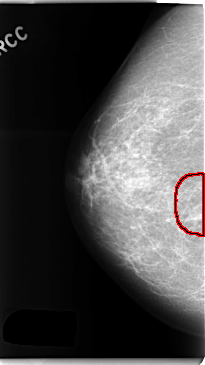

C_0251_1.RIGHT_CC

RIGHT_CC LINES 4736 PIXELS_PER_LINE 2664 BITS_PER_PIXEL 12 RESOLUTION 50 OVERLAY

FILE: C_0251_1.RIGHT_CC.OVERLAY

TOTAL_ABNORMALITIES 1

ABNORMALITY 1

LESION_TYPE MASS SHAPE IRREGULAR MARGINS ILL_DEFINED

ASSESSMENT 4

SUBTLETY 3

PATHOLOGY BENIGN

TOTAL_OUTLINES 1

BOUNDARY